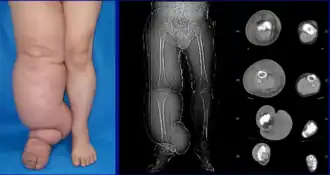

| Lower extremity lymphedema | |

Lymphedema can occur in both the upper and lower extremities, and in some cases, the head and neck. Assessment of the extremities first begins with a visual inspection; color, presence of hair, visible veins, size and any sores or ulcerations are noted. Lack of hair may indicate an arterial circulation problem.[34] In cases of swelling, the extremities' circumference is measured over time for reference. In early stages of lymphedema, elevating the limb may reduce or eliminate the swelling. Palpation of the wrist or ankle can determine the degree of swelling; assessment includes a check of the pulses. The axillary or inguinal lymph nodes may be enlarged due to the swelling. Enlargement of the nodes lasting more than three weeks may indicate infection or other illnesses (such as sequela from breast cancer surgery) requiring further medical attention.[34]

Chronic venous stasis changes can mimic early lymphedema, but are more often bilateral and symmetric. Lipedema can also mimic lymphedema, however lipedema characteristically spares the feet beginning abruptly at the malleolus (ankle).[2] As a part of the initial work-up before diagnosing lymphedema, it may be necessary to exclude other potential causes of lower extremity swelling such as kidney failure, hypoalbuminemia, congestive heart-failure, protein-losing kidney disease, pulmonary hypertension, obesity, pregnancy and drug-induced edema.